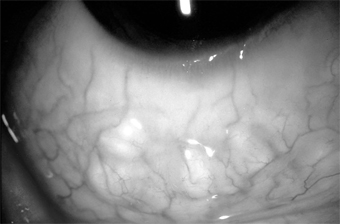

Chapter 5: Conjunctiva III. MISCELLANEOUS DISORDERS OF THE CONJUNCTIVA LYMPHANGIECTASIS Lymphangiectasis is characterized by localized small, clear, tortuous dilations in the conjunctiva. They are merely dilated lymph vessels, and no treatment is indicated unless they are irritating or cosmetically objectionable. They can then be cauterized or excised (Figure 5-23). CONGENITAL CONJUNCTIVAL LYMPHEDEMA This is a rare entity, unilateral or bilateral, and characterized by pinkish, fleshy edema of the bulbar conjunctiva. Usually observed as an isolated entity at birth, the condition is thought to be due to a congenital defect in the lymphatic drainage of the conjunctiva. It has been observed in chronic hereditary lymphedema of the lower extremities (Milroy's disease) and is thought to be an ocular manifestation of this disease rather than an associated anomaly. CYSTINOSIS Cystinosis is a rare congenital disorder of amino acid metabolism characterized by widespread intracellular deposition of cystine crystals in various body tissues, including the conjunctiva and cornea. Three types are recognized: childhood, adolescent, and adult. Life expectancy is reduced in the first two types. SUBCONJUNCTIVAL HEMORRHAGE This common disorder may occur spontaneously, usually in only one eye, in any age group. Its sudden onset and bright red appearance usually alarm the patient. The hemorrhage is caused by rupture of a small conjunctival vessel, sometimes preceded by a bout of severe coughing or sneezing (Figure 5-24). The best treatment is reassurance. The hemorrhage usually absorbs in 2-3 weeks. In rare instances the hemorrhages are bilateral or recurrent; the possibility of blood dyscrasias should then be ruled out. OPHTHALMIA NEONATORUM Ophthalmia neonatorum in its broad sense refers to any infection of the newborn conjunctiva. In its narrow and commonly used sense, however, it refers to a conjunctival infection, chiefly gonococcal, that follows contamination of the baby's eyes during its passage through the mother's cervix and vagina or during the postpartum period. Because gonococcal conjunctivitis can rapidly cause blindness, the cause of all cases of ophthalmia neonatorum should be verified by examination of smears of exudate, epithelial scrapings, cultures, and rapid tests for gonococci. Gonococcal neonatal conjunctivitis causes corneal ulceration and blindness if not treated immediately. Chlamydial neonatal conjunctivitis (inclusion blennorrhea) is less destructive but can last months if untreated and may be followed by pneumonia. Other causes include infections with staphylococci, pneumococci, Haemophilus, and herpes simplex virus and silver nitrate prophylaxis. The time of onset is important but not entirely reliable in clinical diagnosis since the two principal types, gonorrheal ophthalmia and inclusion blennorrhea, have widely differing incubation periods: gonococcal disease 2-3 days and chlamydial disease 5-12 days. The third important birth canal infection (HSV-2 keratoconjunctivitis) has a 2- to 3-day incubation period and is potentially quite serious because of the possibility of systemic dissemination. Treatment for neonatal gonococcal conjunctivitis is with ceftriaxone, 125 mg as a single intramuscular dose; a second choice is kanamycin, 75 mg intramuscularly. To treat chlamydial conjunctivitis in newborns, erythromycin oral suspension is effective at a dosage of 40 mg/kg/d in four divided doses for 2 weeks. In both gonococcal and chlamydial conjunctivitis, the parents need to be treated. Herpes simplex keratoconjunctivitis is treated with acyclovir, 30 mg/kg/d in three divided doses for 14 days. Neonatal disease from HSV requires hospitalization because of the potential neurologic or systemic manifestations. Other types of neonatal conjunctivitis are treated with erythromycin, gentamicin, or tobramycin ophthalmic ointment four times daily. Credé 1% silver nitrate prophylaxis is effective for the prevention of gonorrheal ophthalmia but not inclusion blennorrhea or herpetic infection. The slight chemical conjunctivitis induced by silver nitrate is minor and of short duration. Accidents with concentrated solutions can be avoided by using wax ampules specially prepared for Credé prophylaxis. Tetracycline and erythromycin ointment are effective substitutes. OCULOGLANDULAR DISEASE (PARINAUD'S OCULOGLANDULAR SYNDROME) This is a group of conjunctival diseases, usually unilateral, characterized by low-grade fever, grossly visible preauricular adenopathy, and one or more conjunctival granulomas (Figure 5-25). The commonest cause is cat-scratch disease, but there are many other causes, including Mycobacterium tuberculosis, Treponema pallidum, Francisella tularensis, Pasteurella (Yersinia) pseudotuberculosis, Chlamydia trachomatis serotypes L1, L2, and L3, and Coccidioides immitis. Conjunctival Cat-Scratch Disease This protracted but benign granulomatous conjunctivitis is found most commonly in children who have been in intimate contact with cats. The child often runs a low-grade fever and develops a reasonably enlarged preauricular node and one or more conjunctival granulomas. These may show focal necrosis and may sometimes ulcerate. The regional adenopathy does not suppurate. The clinical diagnosis is supported by serology. The disease appears to be caused by a slender pleomorphic gram-negative bacillus (Bartonella [formerly Rochalimaea] henselae), which grows in the walls of blood vessels. With special stains, this organism can be seen in biopsies of conjunctival tissue. The organism closely resembles Leptotrichia buccalis, and the disease was previously known as leptotrichosis conjunctivae (Parinaud's conjunctivitis). The organism is commonly found in the mouth in humans and always in the mouth in cats. The eye may be contaminated by saliva on the child's fingers or by cat saliva on the child's pillow. Afipia felis has been incriminated also and may still play a role. The disease is self-limited (without corneal or other complications) and resolves in 2-3 months. The conjunctival nodule can be excised; in the case of a solitary granuloma, this may be curative. Systemic tetracyclines may shorten the course but should not be given to children under 7 years of age. Conjunctivitis Secondary to Neoplasms (Masquerade Syndrome) When examined superficially, a neoplasm of the conjunctiva or lid margin is often misdiagnosed as a chronic infectious conjunctivitis or keratoconjunctivitis. Since the underlying lesion is often not recognized, the condition has been referred to as masquerade syndrome. The masquerading neoplasms on record are conjunctival capillary carcinoma, conjunctival carcinoma in situ, infectious papilloma of the conjunctiva, sebaceous gland carcinoma, and verrucae. Verrucae and molluscum tumors of the lid margin may desquamate toxic tumor material that produces a chronic conjunctivitis, keratoconjunctivitis, or (rarely) keratitis alone. PREVIOUS | NEXT Page: 1 | 2 | 3 | 4 | 5 | 6 | 7 | 8 | 9 | 10 | 11 | 12 | 13 | 14 10.1036/1535-8860.ch5 |